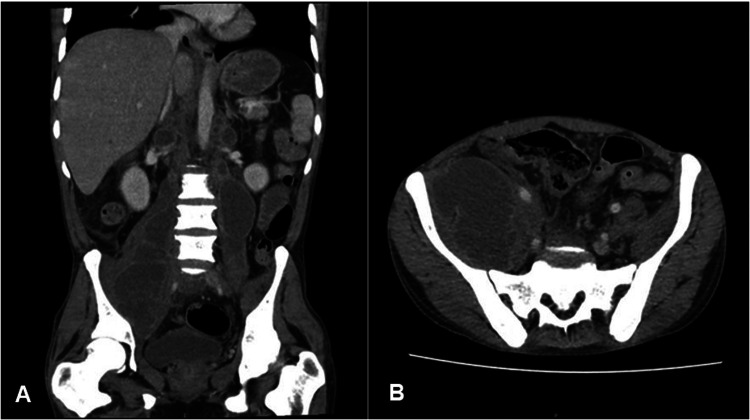

Immune reconstitution inflammatory syndrome is a common manifestation in human immunodeficiency virus (HIV)-positive patients infected with tuberculosis (TB). One of the unusual complications of this condition is the development of psoas abscess. We describe a case of immune reconstitution inflammatory syndrome (IRIS) in a patient with disseminated TB under treatment, HIV-positive with a low CD4 cell count, complicated by bilateral psoas abscess. Our patient presented with fever, abdominal pain, and lymphadenopathy, typical symptoms of TB-IRIS. Diagnosis was confirmed by surgical drainage of the abscess of the right iliac psoas muscle with detection of acid-fast bacteria on Ziehl-Neelsen staining and negative culture of purulent discharge. Treatment with prednisone was started in addition to continuation of antituberculosis therapy and antiretroviral therapy.